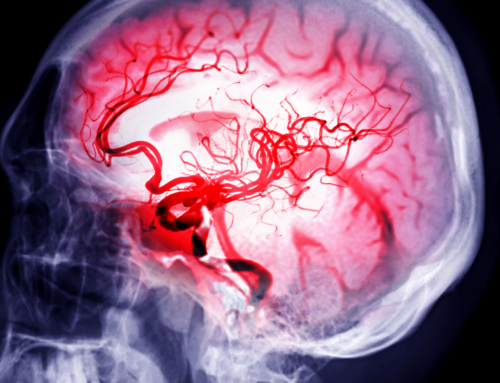

The program, called International Essential Stroke Life Support (ESLS), is designed to help paramedics diagnose stroke patients faster.

“Time is tissue. So the longer it takes, the more brain tissue dies. And unfortunately, brain tissue is one of those tissues that does not regenerate. So once it’s gone, it’s gone. So the sooner we are to identify and treat, the better the outcome they’re going to have,” Mayfield said.

Stroke is the fifth-leading cause of death in the United States and the leading cause of long-term disability.